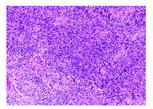

患者 男,64岁,因阵发性头痛、肢体抽搐1月余于2020年1月12日入院。既往体健,否认结核等病史,近期亦无发热、咳嗽情况。体检:体温36.8 ℃,血压120/80 mmHg(1 mmHg=0.133 kPa),神志清楚,记忆力减退,反应迟钝,余未见明显阳性体征。实验室检查:血常规、血清肿瘤标志物筛查等均为正常值,结核T细胞斑点试验(-)。胸腹部CT平扫、肝胆胰脾肾超声等检查未见明显异常。颅脑MRI提示颅内脑实质及脑膜多发异常强化病灶(图1),术前诊断考虑转移瘤可能性大、结核待排。综合考虑手术风险及重要神经功能损伤、同时明确病理诊断等因素后决定切除较大的左颞枕叶病灶。采用神经导航引导下经左颞枕马蹄形切口入路全切除左侧颞枕叶占位病变,术中见病变组织呈鱼肉样,色灰白,质地偏韧,边界不清楚,血供较丰富,病变内部含坏死组织。术后病理诊断为GS:肿瘤细胞呈梭形,胞界不清,胞浆嗜酸,核梭形或不规则形,呈片状或束状分布,可见瘤巨细胞;小血管呈簇状增生,可见栅栏状坏死(图2)。免疫组化染色显示胶质纤维酸性蛋白及波形蛋白阳性。术后予以防治癫痫、补液等治疗,2周后患者头痛症状改善,转肿瘤科行辅助放疗和替莫唑胺化疗。术后第5个月电话随访,患者病情恶化放弃继续术后辅助治疗。

GS是中枢神经系统罕见的恶性肿瘤,占全部胶质母细胞瘤的1.8%~8.0%,少数可以在原发时即为GS,多数是胶质瘤术后或是放疗后继发演变而来[2,3],组织病理学表现为胶质瘤和肉瘤的特点[4,5]。胶质瘤成分上为神经胶质纤维酸性蛋白阳性;肉瘤部分富含网状纤维,由神经胶质纤维酸性蛋白阴性的梭形细胞密集束状排列而成,细胞核有不典型性,核分裂象多并有坏死,是病理诊断GS的重要依据。发病人群以中年男性为主,婴幼儿亦可发病。GS与胶质母细胞瘤和星形细胞瘤的病程经过及临床症状相似,多数病程短且无明显特异性表现,部分患者存在神经轴及肝、肺、淋巴结等颅外转移倾向,这主要由其肉瘤部分决定[6]。GS影像学表现复杂多样,确诊仍需病理定性,典型影像学特征为[2,7,8,9]:GS呈类圆形或不规则形;CT表现与一般恶性胶质瘤类似;MRI多表现为T1像呈低信号,T2像呈混杂稍高信号或高信号,信号不均,中央部分坏死囊变,瘤周不同程度水肿,占位效应明显;增强扫描呈环形、花环状强化,部分呈不均匀强化。目前GS多见于大脑半球,特别是颞叶,绝大部分病灶为单发且多靠近脑表面,仅有少数个案报道称有多发GS[10,11]。本例患者病灶数量远多于目前已有报道,病灶分布于左侧颞枕叶、海马、大脑大静脉池、桥前池、鞍上池,呈现颅内多发脑实质及脑膜异常强化病灶,弥漫多发样改变,病灶数目极为罕见,病灶所在位置亦少见。由于GS临床相对较少的特性且该病影像表现有时与大脑半球的其他占位性疾病,如胶质母细胞瘤、原发性中枢神经系统淋巴瘤、脑脓肿、结核、梅毒、转移瘤等极为相像,因此术前诊断较为困难,极易出现误诊。本例患者术前就曾数次在外院及我院被诊断为转移瘤可能性大、结核待排。由于术前考虑恶性病变可能,病灶多发且分布较散、部分位置深在,全切可能性不大;但为了一定程度上解除病灶占位效应缓解颅高压症状并明确病理诊断,最终选择孤立的颞枕叶大病灶进行切除。术中病理亦考虑高级别胶质瘤可能,故没有继续另行术口切取其他部位病灶以避免增加医源性创伤。本例患者无颅脑肿瘤及放射治疗病史,其发病年龄、性别及肿瘤原发部位与既往文献报道相似,故颞枕叶病灶属原发性GS可能性较大。与胶质母细胞瘤相比,GS更易发生颅内外转移,但仅根据影像学表现难以准确判断海马、脑池等处的病灶是否是脑脊液播散转移而形成,进一步研究需行更为详实全面的病理检查。